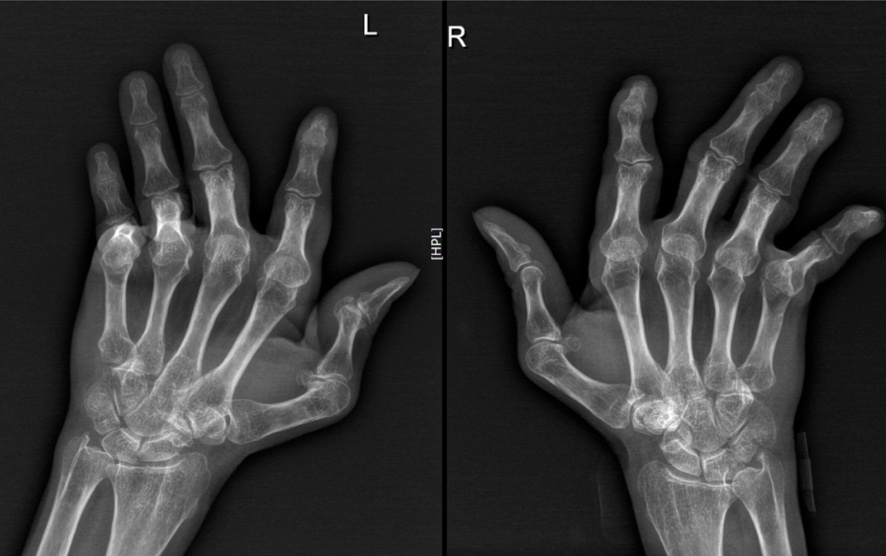

被当作“类风关”治疗30年,直到双小腿大面积溃疡后才明确诊断

王阿姨30年前因关节变形被诊断为“类风湿关节炎”,长期服用小剂量激素治疗,但关节畸形并未好转。3年前,她因右股骨头坏死做了置换手术。一年半前,右脚踝外侧出现小片皮肤溃疡,外院诊断为“静脉曲张性溃疡”,但溃疡面积不断扩大,疼痛加剧,最终只能依赖轮椅出行。走投无路的王阿姨来到瑞金医院皮肤科郑捷教授的门诊。